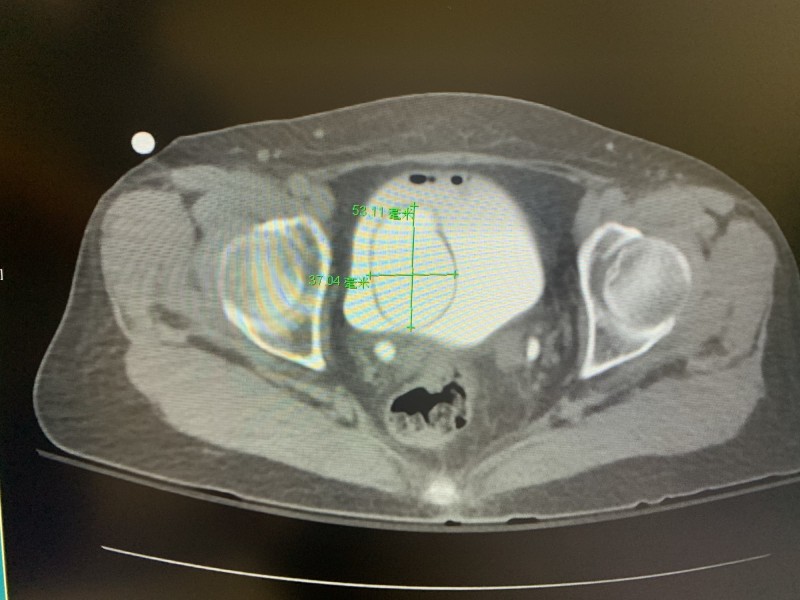

〔記者方志賢/高雄報導〕高雄一名67歲婦女,2年多前有一腫塊從尿道口突出,她靠自己把它塞回去,最近腫塊愈變愈大,怎麼用力也推不回去,嚇得趕緊就醫,醫師發現她的輸尿管長了5公分的囊腫,並從不到1公分寬的尿道口跑出來,尿液從腎臟經膨出的輸尿管,再繞回體內膀胱,儲滿後由尿道排出體外,過程「九彎十八拐」,也因此造成漏尿及解尿不順等問題。

這名婦人生產過四胎,她的輸尿管末端與膀胱交接處長了一個囊腫(囊狀膨出),膨出的大小約0.5公分至5公分,由於尿液時多時少,尿液少的時候,囊腫較小就從1公分寬尿道口膨出,後來尿液把囊腫空間繼續充填,囊腫愈變愈大,無法從尿道口縮回去,膨出在尿道口外,導致膀胱、尿道曲折不順暢,以及膀胱出口阻塞,而造成尿意滯留等問題。

沈元琦表示,輸尿管囊腫從尿道口外翻脫垂從外觀不易辨認,若沒有正確診斷,很容易誤以為是膀胱或子宮脫垂,經電腦斷層檢查才診斷出是輸尿管囊腫從尿道口外翻脫垂的罕見案例。